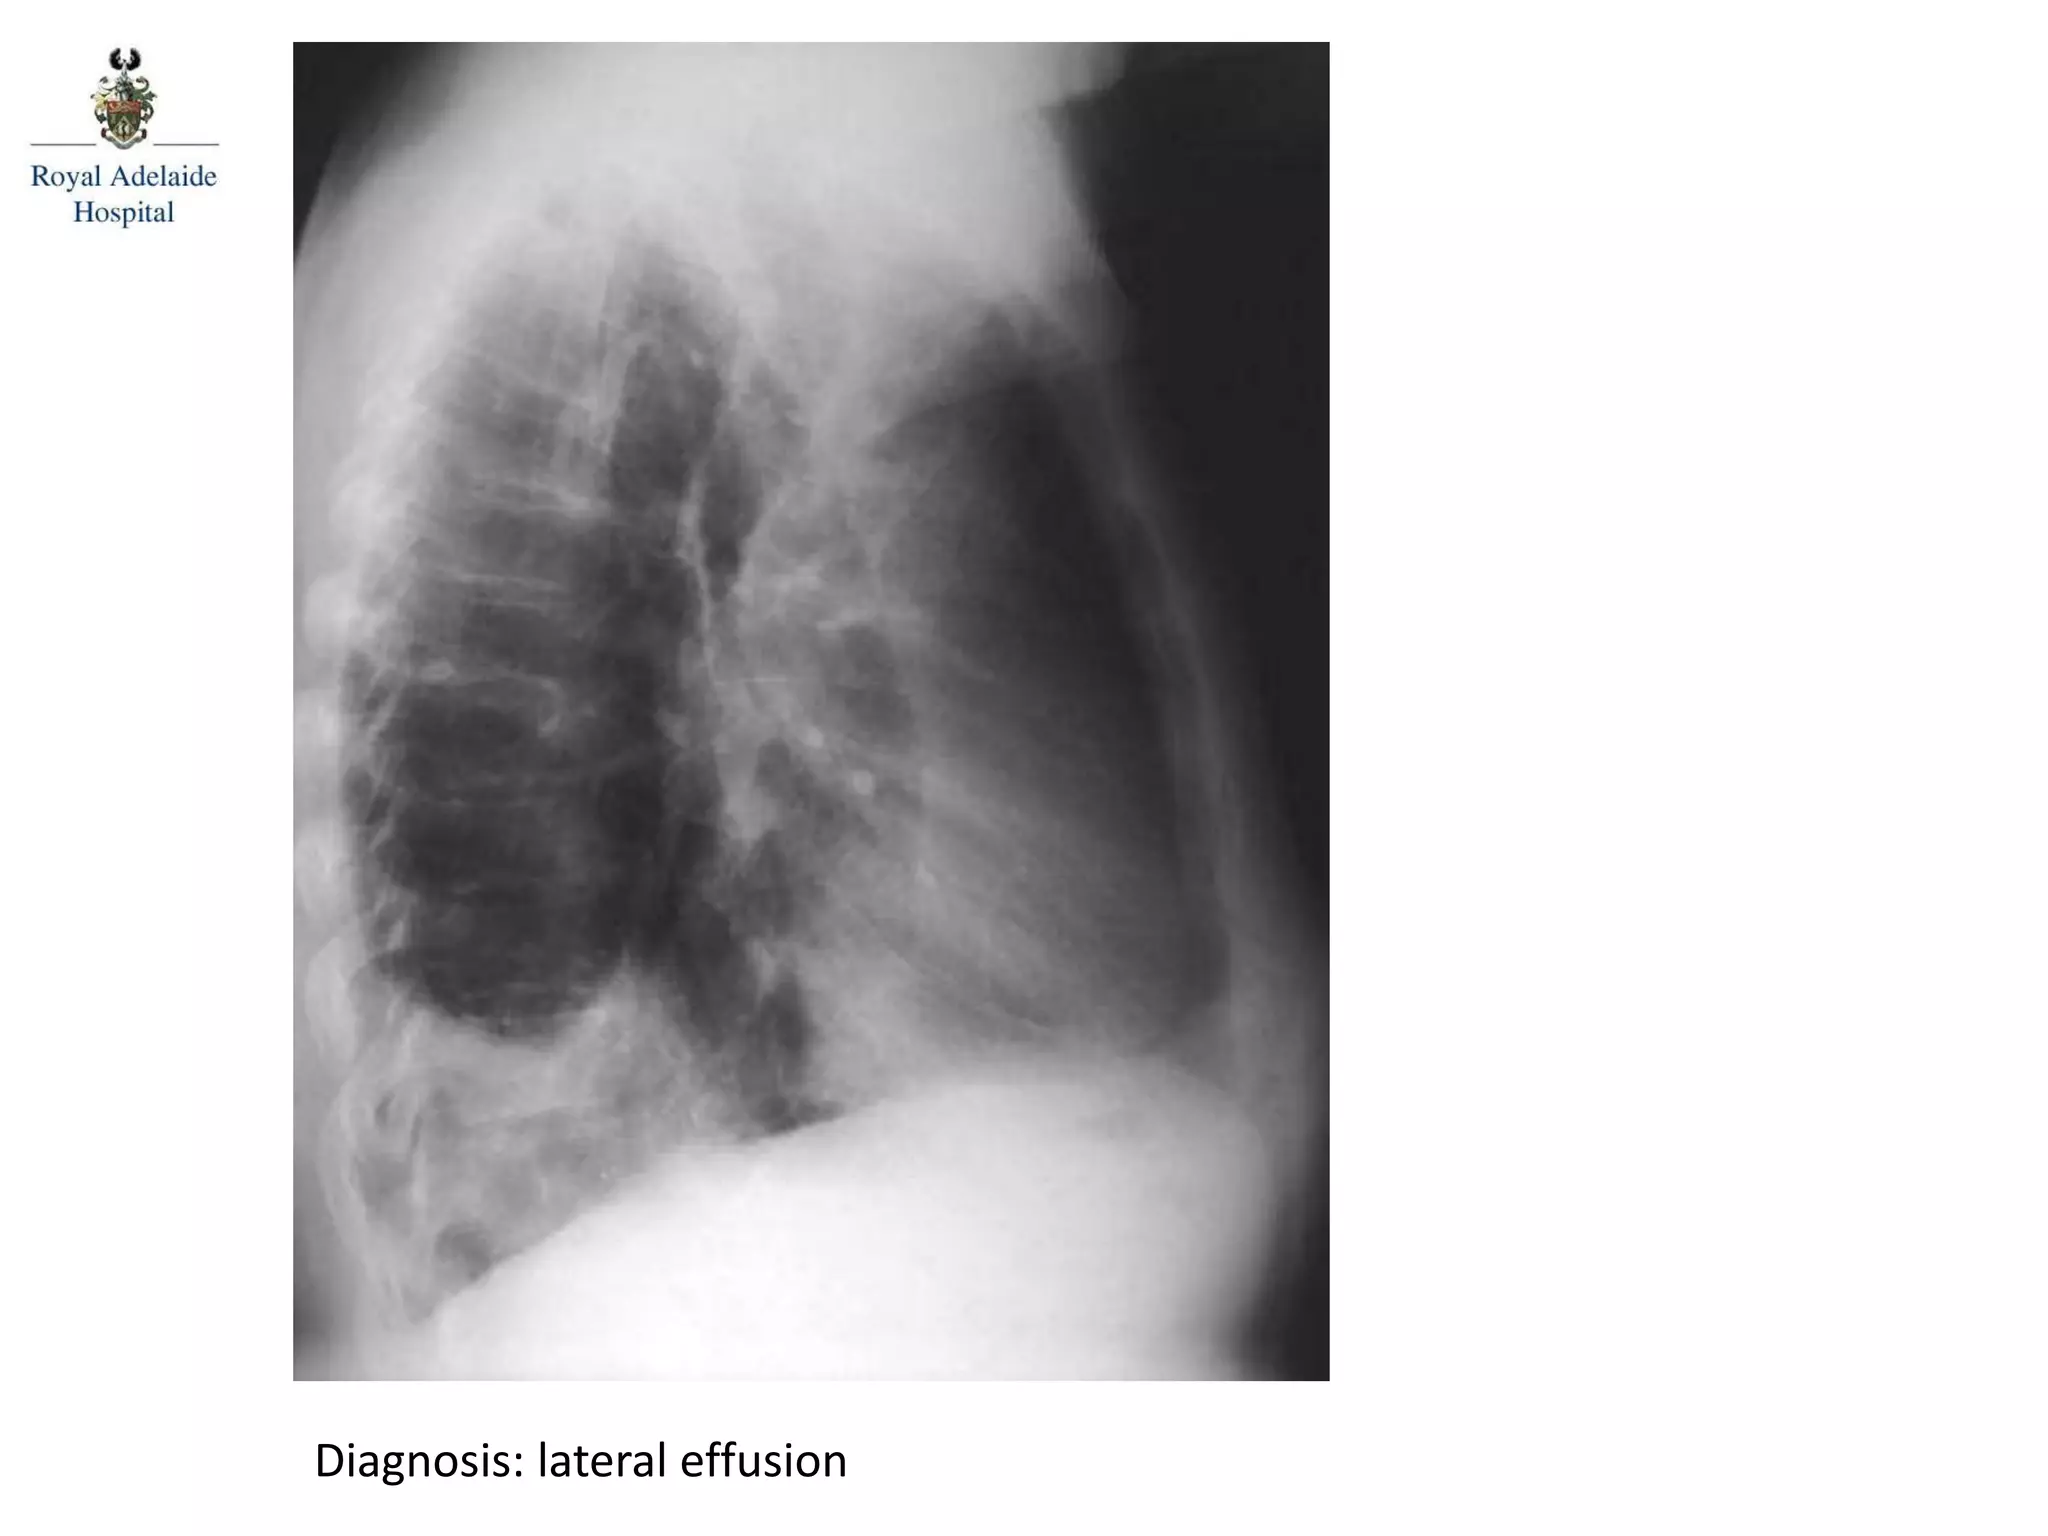

Diagnosis: lateral effusion